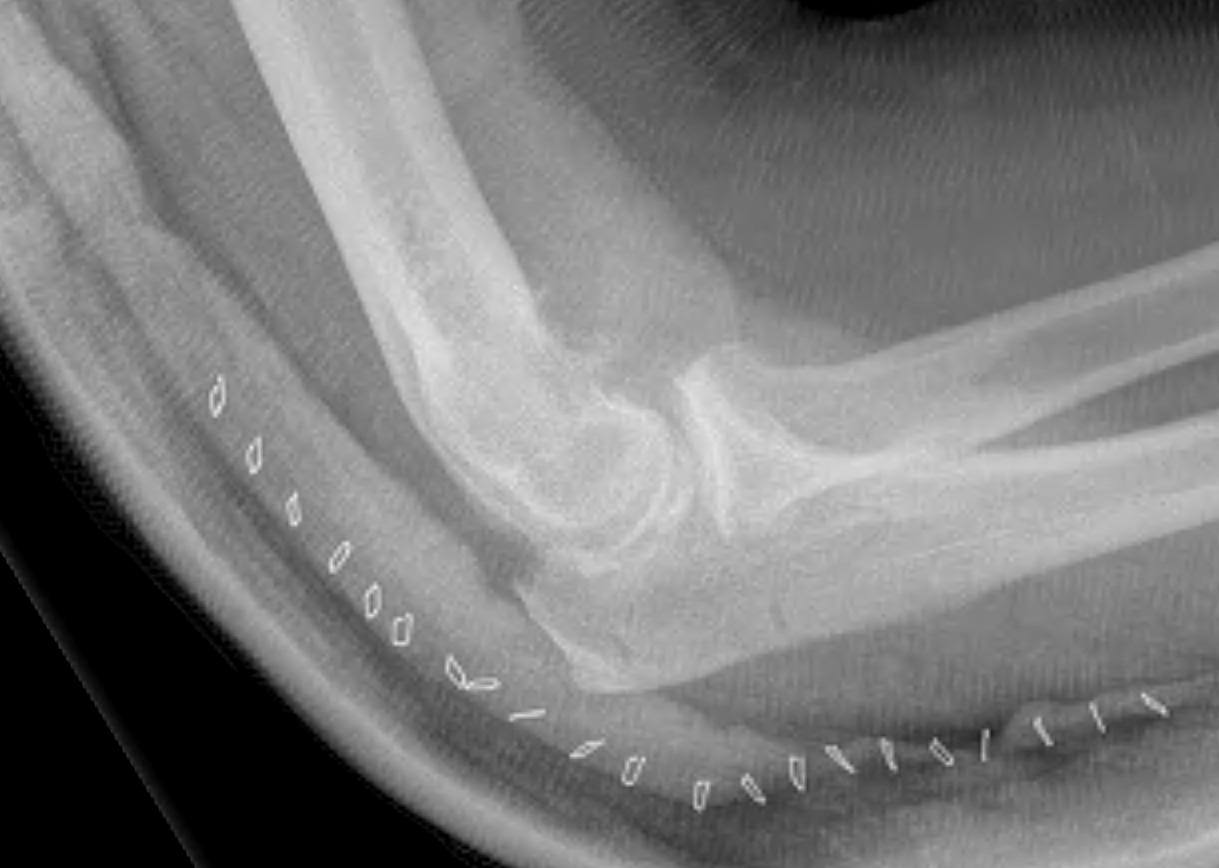

CT

Define olecranon and coranoid process osteophytes

Identification loose bodies

Osteophyte of the olecranon likely impinging in extension

CT demonstrating loose bodies in the ulnohumeral joint

Multiple loose bodies in anterior and posterior elbow joint